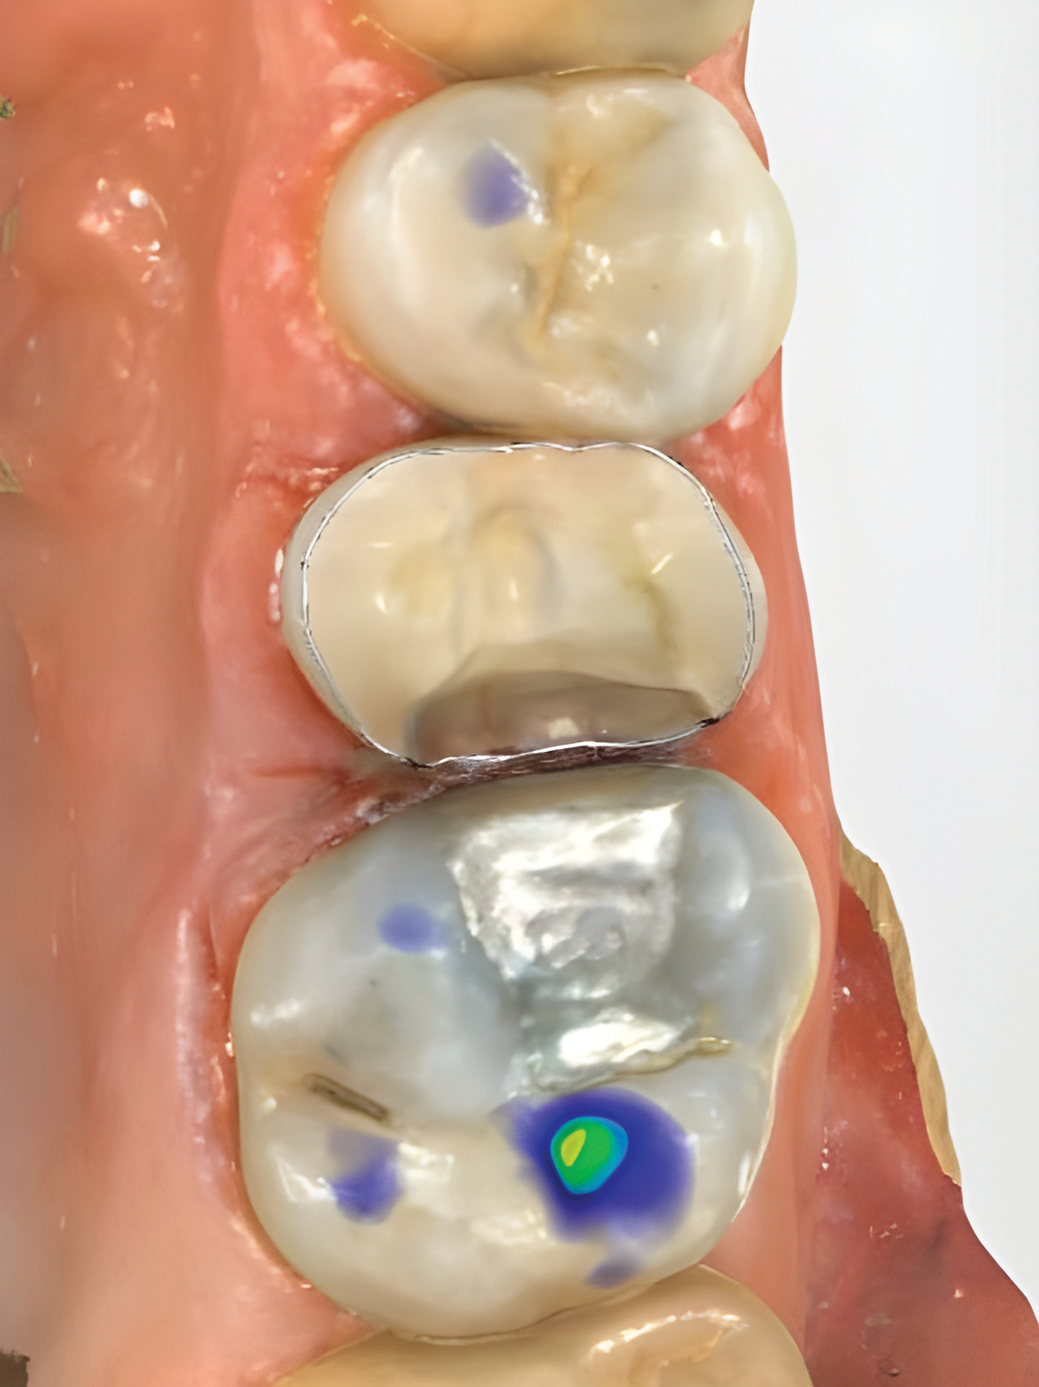

IOSs have found extensive applications across various dental specialties.1 In restorative dentistry, they are primarily used for fabricating dental restorations through CAD/CAM workflows, which remains by far their most widespread use (Figure 1 through Figure 5).2 The accuracy of IOSs enables dental professionals to produce restorations with precision that is on par with conventional methods.3 In addition to restorative dentistry, IOSs are being utilized for various applications in prosthodontics, orthodontics, forensic dentistry, and oral and maxillofacial surgery.

Fig 1 through Fig 5. Single-visit restoration of a maxillary second premolar following root canal treatment. Fig 1: Morphology-guided overlay preparation. Fig 2: IOS bite registration via imaging of buccal tooth surfaces. Fig 3: Preparation margin defined following IOS impression. Fig 4: Overlay design on the IOS platform, integrating adjacent tooth anatomy. Fig 5: Bonded overlay fabricated from CAD/CAM resin-based composite. Fig 6 through Fig 9. Digital workflow for guided endodontics using a digital twin, created by registering an IOI with CBCT data.